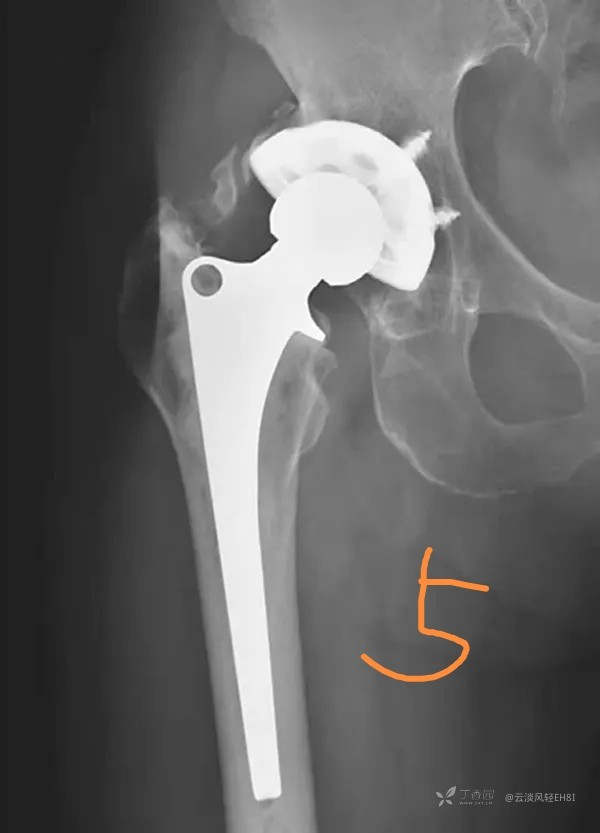

四、异位骨化(图5)

全髋关节置换术后,大约有39%以上的患者可发生邻近软组织骨化,术后2~4周的X线片上常能表现出来,而骨化灶成熟要1年以上时间。X线片上表现股骨假体颈部的周围可见斑片状或条片状骨化阴影,大小范围不一。